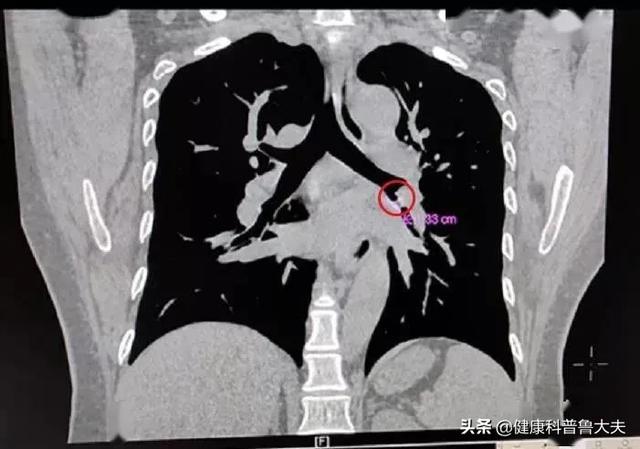

まず、最近咳がひどい人は、呼吸器科に行くことをお勧めします。例えば、肺腫瘍があるかどうか、変則的な咳があるかどうか、その他の病気の原因などです。どのようにチェックするかについては、患者の具体的な状況に応じて、胸部CTや肺機能などの検査を行うかどうかを決定します。総合的に判断すると、咳が非常に強い場合は、まず呼吸器科に行って呼吸器疾患をチェックするのが適切かつ合理的です。

例えば、肺がんの患者の場合、頻繁な咳は外科的な方法で適時にがんをそのまま除去し、その後、放射線治療と化学療法を組み合わせてがんの再発の可能性を減らすため、治療を受けてもよい。